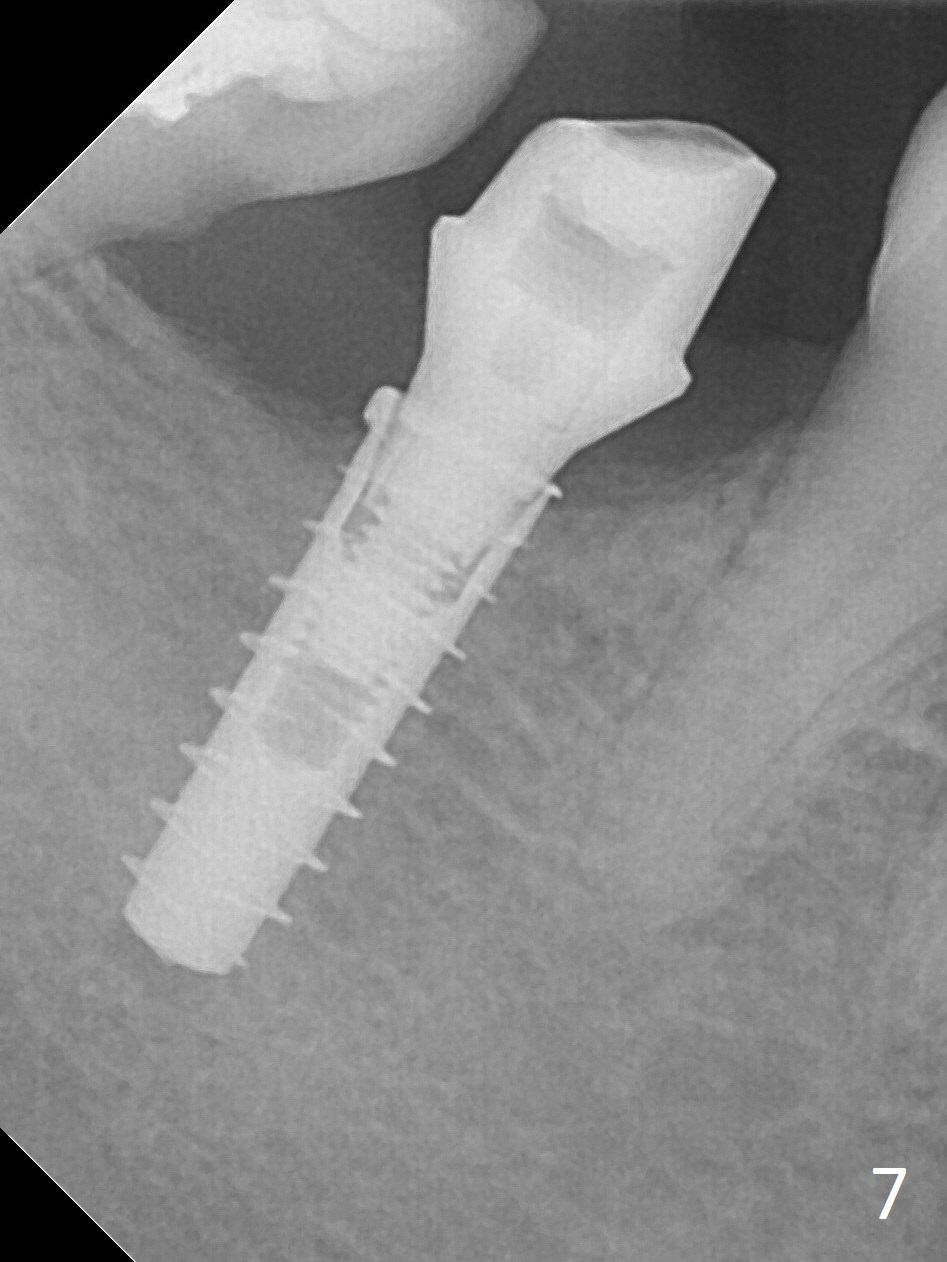

The ridge at #31 is also narrow buccolingually (Fig.1 *). After incision and 1.6 mm pilot drill, a guide pin with 7 mm length is inserted to confirm trajectory and depth; it appears that 11 mm osteotomy has enough clearance from the superior border of the Inferior Alveolar Canal (IAC, Fig.2 red dashed line). Following Marking Bur, 3.3 mm Magic Drill and final drill, the buccal plate seems to be thin (Fig.3 *). When a 4x11 mm IBS implant and 5x4(2) mm pair abutment are placed, the distal thread is exposed (Fig.4 >), the abutment contacts the opposing tooth (data not shown) and there is 2.7 mm clearance from IAC. After increasing the osteotomy 1-2 mm, the implant is placed deeper; the autogenous bone with Osteogen is placed around the plateau of the implant (Fig.5 >), particularly buccally, followed by collagen membrane. When sutures are placed around the abutment, the buccal ridge looks bulkier (Fig.6) than preop (Fig.1). It may remains so long term. The flap surgery makes it possible for simultaneous GBR and reduction in possibility of peri-implantitis. Last, periodontal dressing is applied.